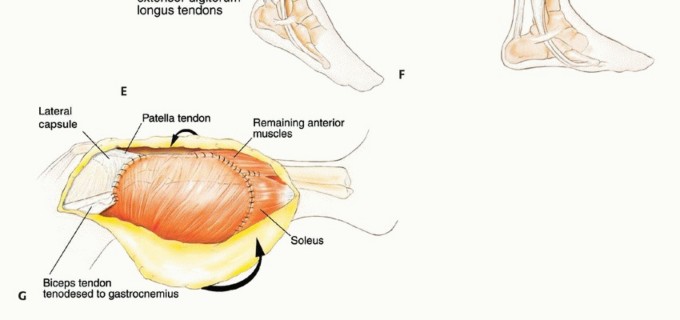

الاستئصال من النوع الأول (Type I Resection):

- الإشارة: يُستخدم لعلاج الأورام الحميدة العدوانية والأورام الغرنية منخفضة الدرجة التي تسببت في تدمير قشري كبير للشظية القريبة.

- الإجراء: يشمل إزالة الشظية القريبة، وغلاف عضلي رقيق من جميع الأبعاد، وموقع ارتباط الرباط الجانبي الوحشي (LCL). يتم الحفاظ على العصب الشظوي المشترك وفروعه الحركية، ويتم استئصال المفصل الظنبوبي الشظوي داخل المفصل.

- الحفاظ: يتم الحفاظ على العصب الشظوي والشريان الظنبوبي الأمامي عادةً.

التحضير لجراحة استئصال ورم الشظية

يتطلب التحضير لجراحة استئصال ورم الشظية تخطيطًا دقيقًا لضمان أفضل النتائج وتقليل المضاعفات. يحرص الأستاذ الدكتور محمد هطيف وفريقه على إعداد المريض بشكل شامل قبل الجراحة.

وضعية المريض

يُستخدم وضع شبه الاستلقاء (رفع الجانب الذي سيتم إجراء الجراحة عليه بزاوية 45 درجة) للسماح بالوصول السهل إلى الحجرات الأمامية والجانبية، وكذلك للسماح بتشريح المساحة المأبضية. يتم تضمين الطرف بأكمله، من الرباط الأربي إلى القدم، في الحقل المعقم. هذا يسمح بتقييم نبضات القدم البعيدة وتنفيذ بتر فوق الركبة إذا لزم الأمر، على الرغم من أن هذا نادر الحدوث بفضل التقنيات الحديثة.

الشق الجراحي (القطع الجراحي)

يُستخدم "الشق الشظوي النفعي" (utilitarian fibular incision)، والذي يسمح بكشف واستئصال الأورام في جميع مستويات الشظية. يمتد هذا الشق من العضلة ذات الرأسين فوق مفصل الركبة، فوق الجزء الأوسط من الشظية، إلى الأمام باتجاه قمة الظنبوب، ثم ينحني خلفيًا وبعيدًا إلى الكاحل. يسمح هذا بتطوير سدائل جلدية عضلية أمامية وخلفية كبيرة.